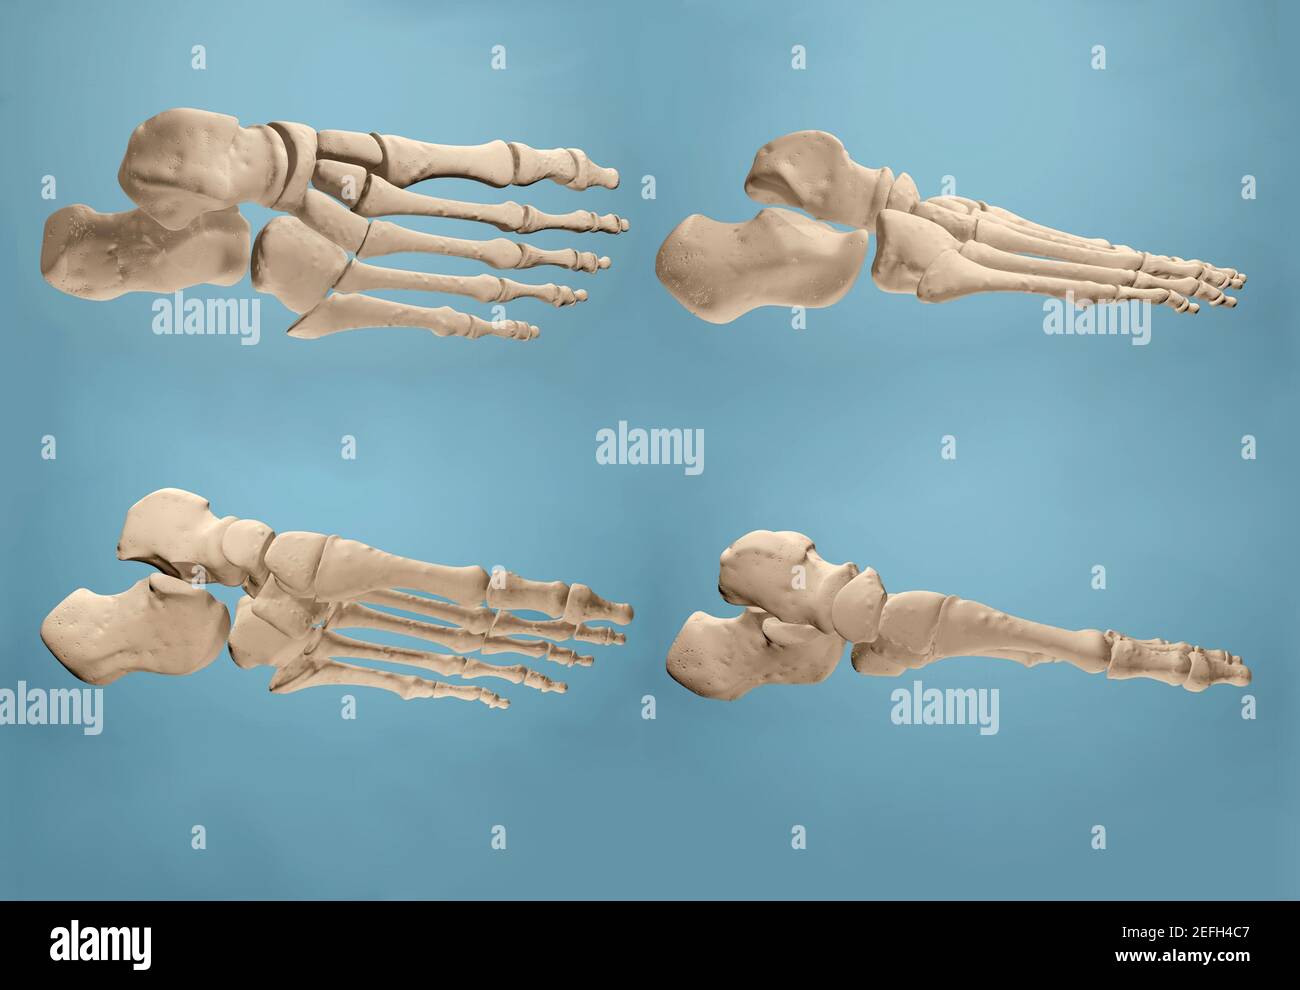

RF2K3D0JF–Illustration du rendu de l'hallux valgus ou du Boignon 3D. Vue supérieure ou dorsale des os du pied gauche humains avec contours du corps sur fond bleu. Un

RF2K3D0JE–Illustration du rendu de l'hallux valgus ou du bunion x-ray 3D. Vue dorsale ou de dessus du pied gauche en bonne santé et blessé sur fond bleu. Anatomie, ostéol

RF2EFH4NT–Affiche prête pour la salle de classe montrant les os du pied dans des vues anatomiques et éclatées.